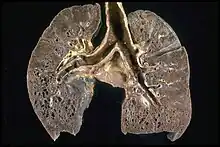

Gross pathology image showing sarcoidosis with honeycombing: Prominent honeycombing is present in the lower lobes accompanied by fibrosis and some honeycombing in the upper lungs. Honeycombing consists of cystically dilated airways separated by scar tissue resembling the honeycomb of bees. It is a nonspecific end stage of many types of interstitial lung disease.

The disease can remit spontaneously or become chronic, with exacerbations and remissions. In some cases, it can progress to pulmonary fibrosis and death. In benign cases, remission can occur in 24 to 36 months without treatment but regular follow ups are required. Some cases, however, may persist several decades.[19] Two-thirds of people with the condition achieve a remission within 10 years of the diagnosis.[145] When the heart is involved, the prognosis is generally less favourable, though corticosteroids appear effective in improving AV conduction.[146][147] The prognosis tends to be less favourable in African Americans than in white Americans.[26] In a Swedish population-based analysis, the majority of cases who did not have severe disease at diagnosis had comparable mortality to the general population.[148] The risk for premature death was markedly (2.3-fold) increased compared to the general population for a smaller group of cases with severe disease at diagnosis.[148] Serious infections, sometimes multiple during the course of disease, and heart failure might contribute to the higher risk of early death in some patients with sarcoidosis.[149][150]